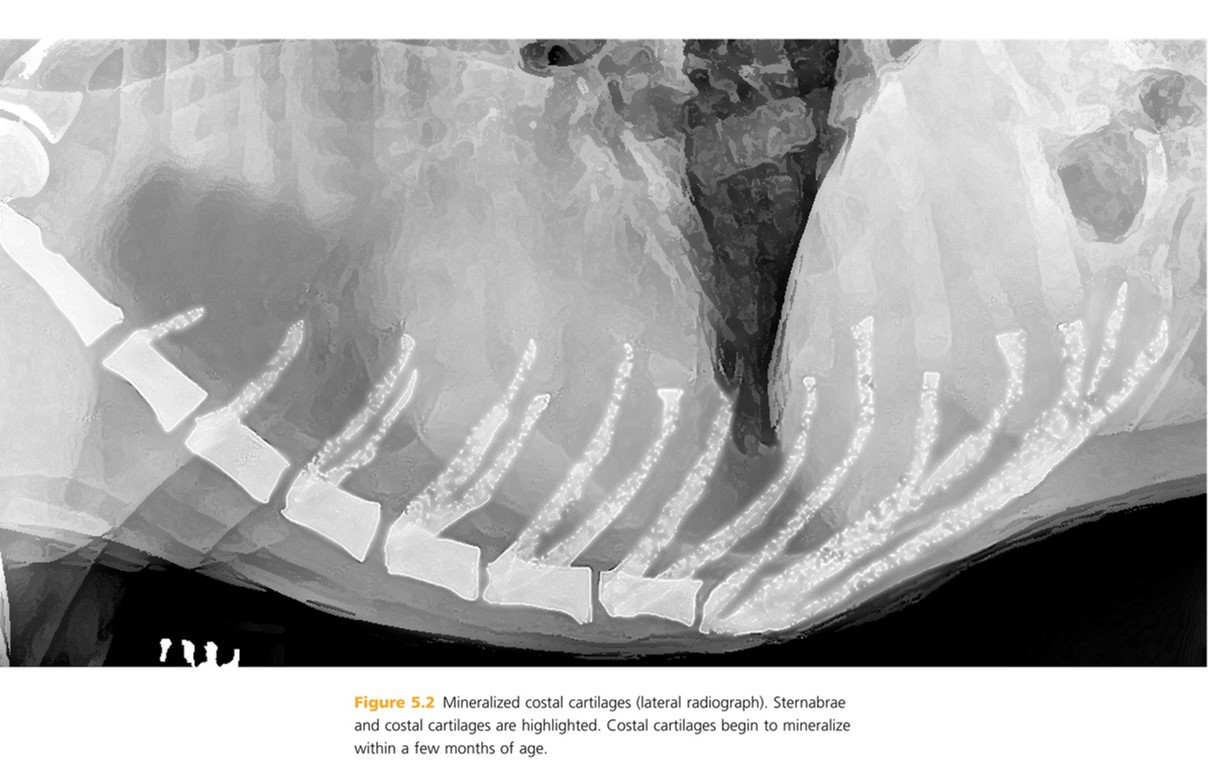

Costal cartilages extend from distal end of each rib to ______.

pg. 277 sternum